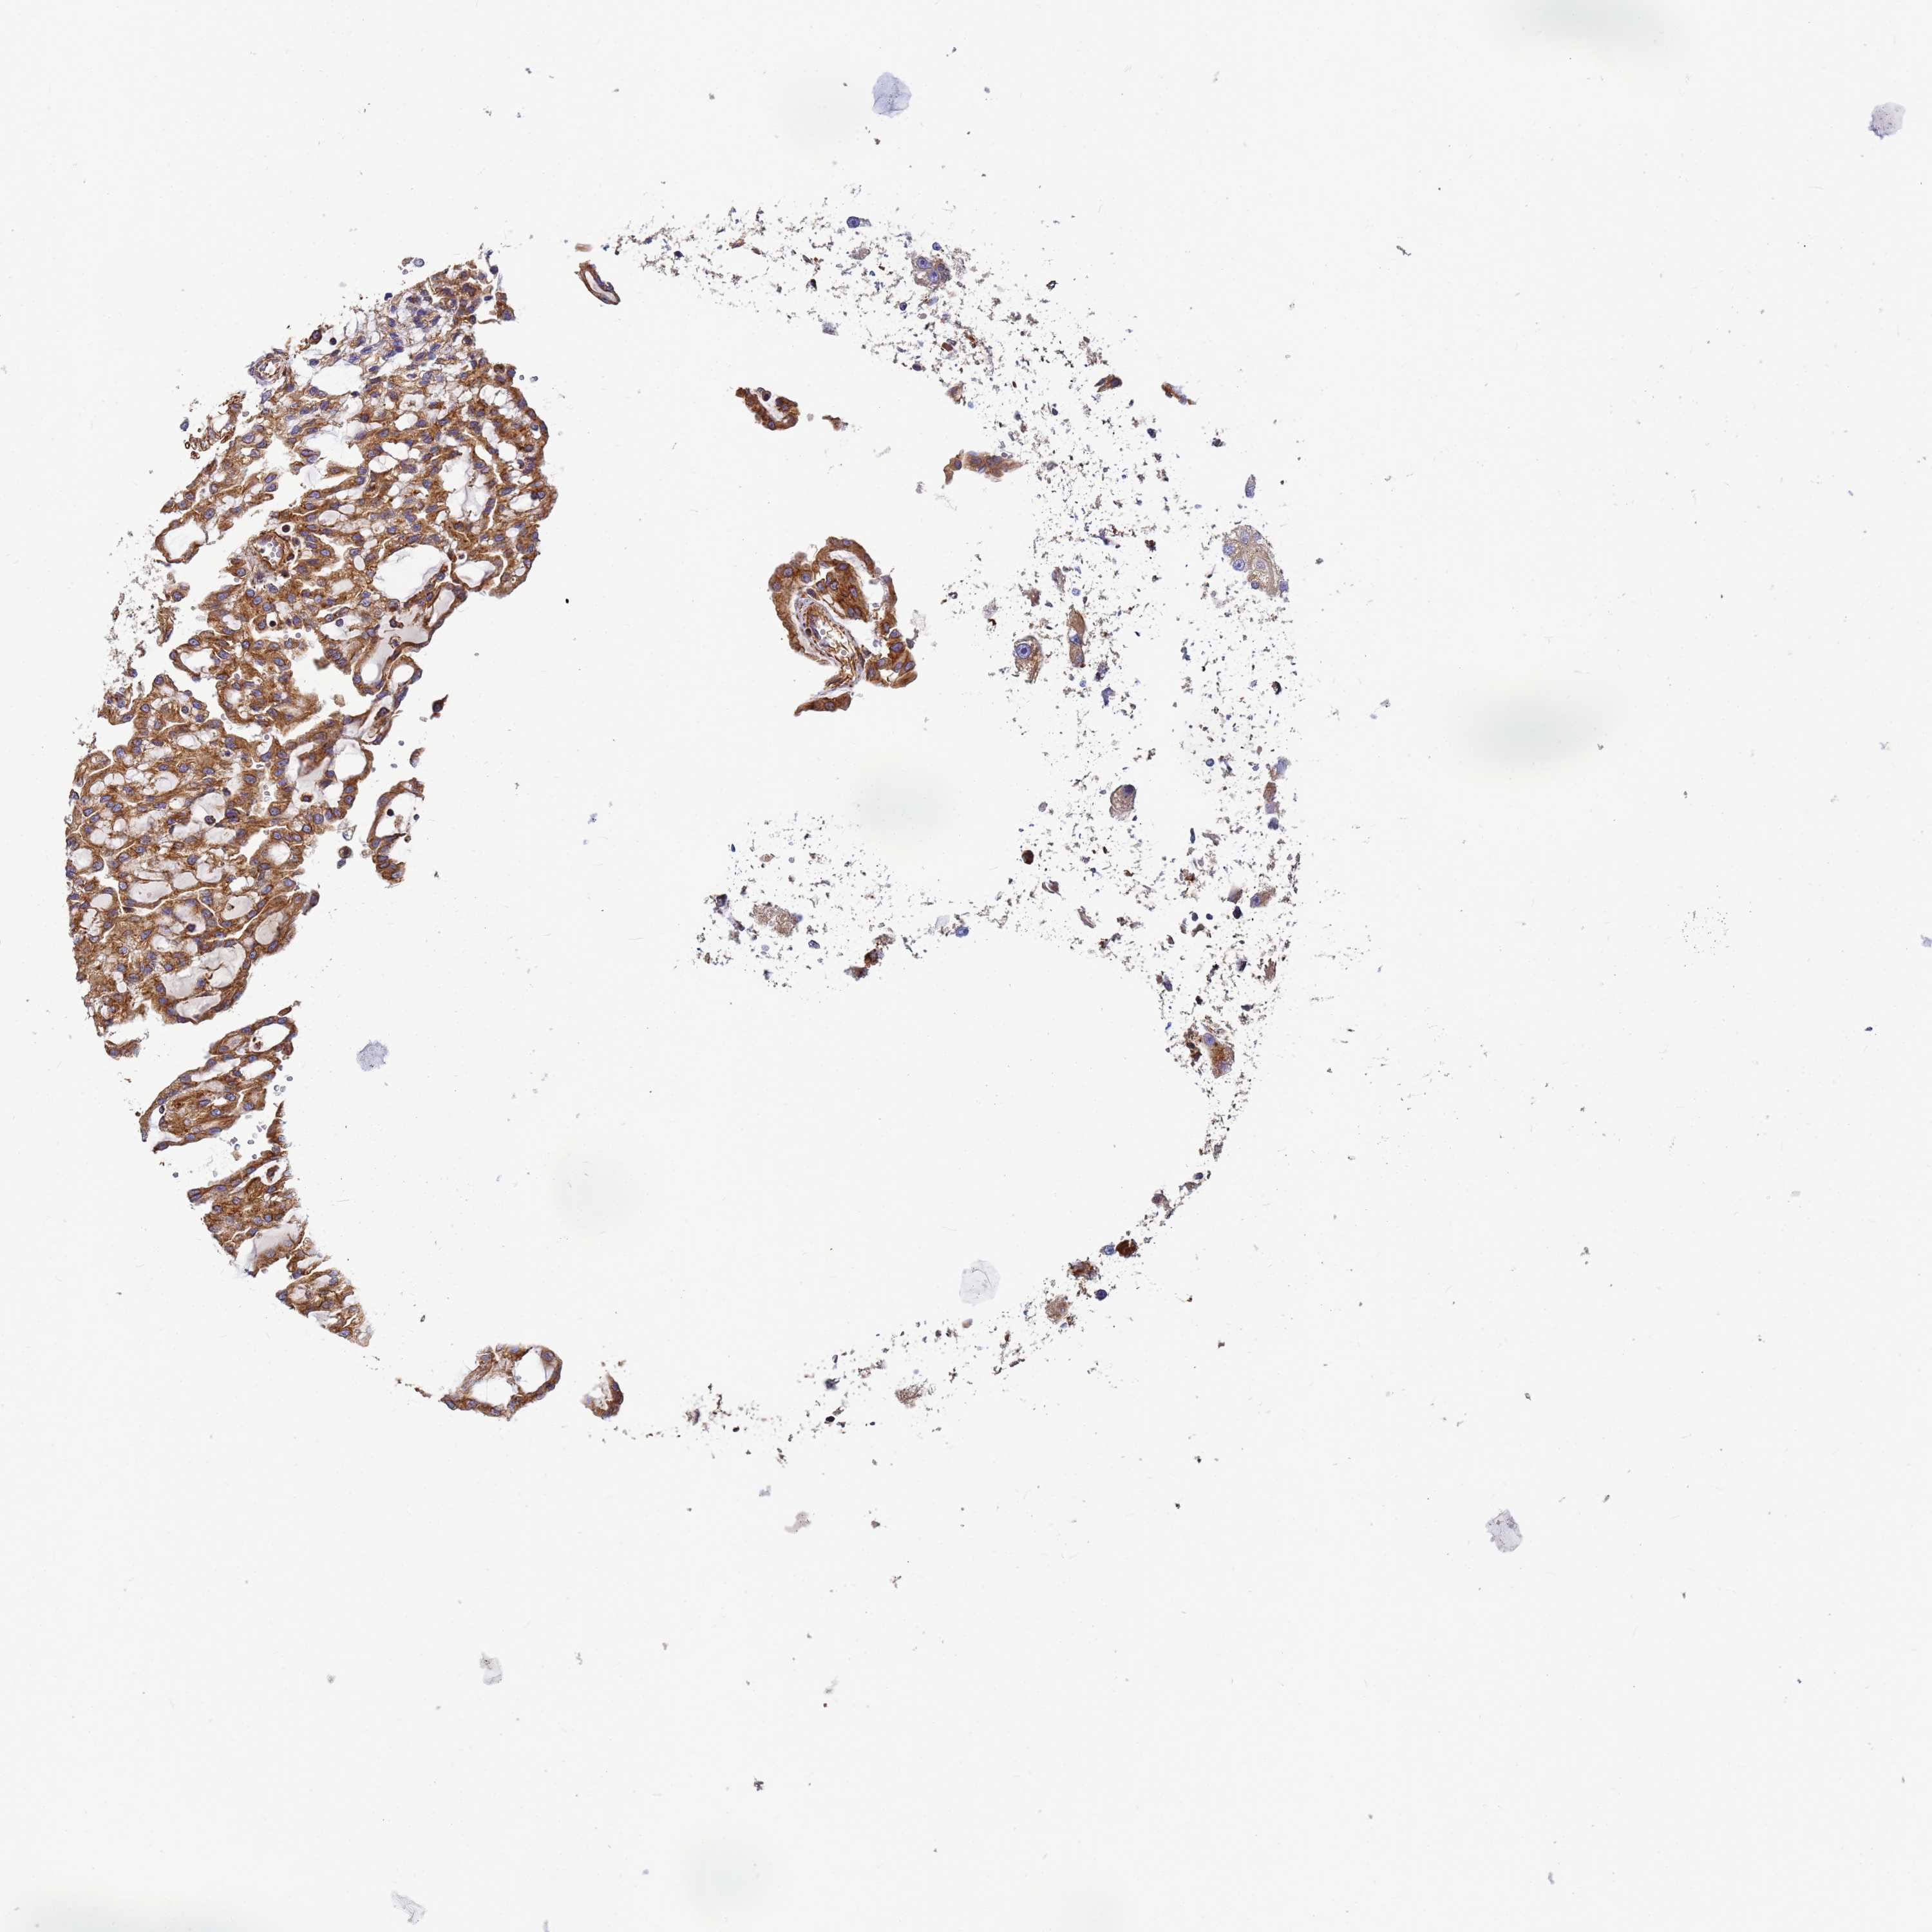

KIDNEY RENAL CLEAR CELL CARCINOMA (VALIDATION) - Interactive survival scatter ploti

& Survival analysisi

Kaplan-Meier plots summarize results from analysis of correlation between mRNA expression level and patient survival. Patients were divided based on level of expression into one of the two groups "low" (under cut off) or "high" (over cut off). X-axis shows time for survival (years) and y-axis shows the probability of survival, where 1.0 corresponds to 100 percent.

C2CD5 is not prognostic in Kidney Renal Clear Cell Carcinoma (validation)

: 26.24

Average pTPM 24.8

Number of samples 100